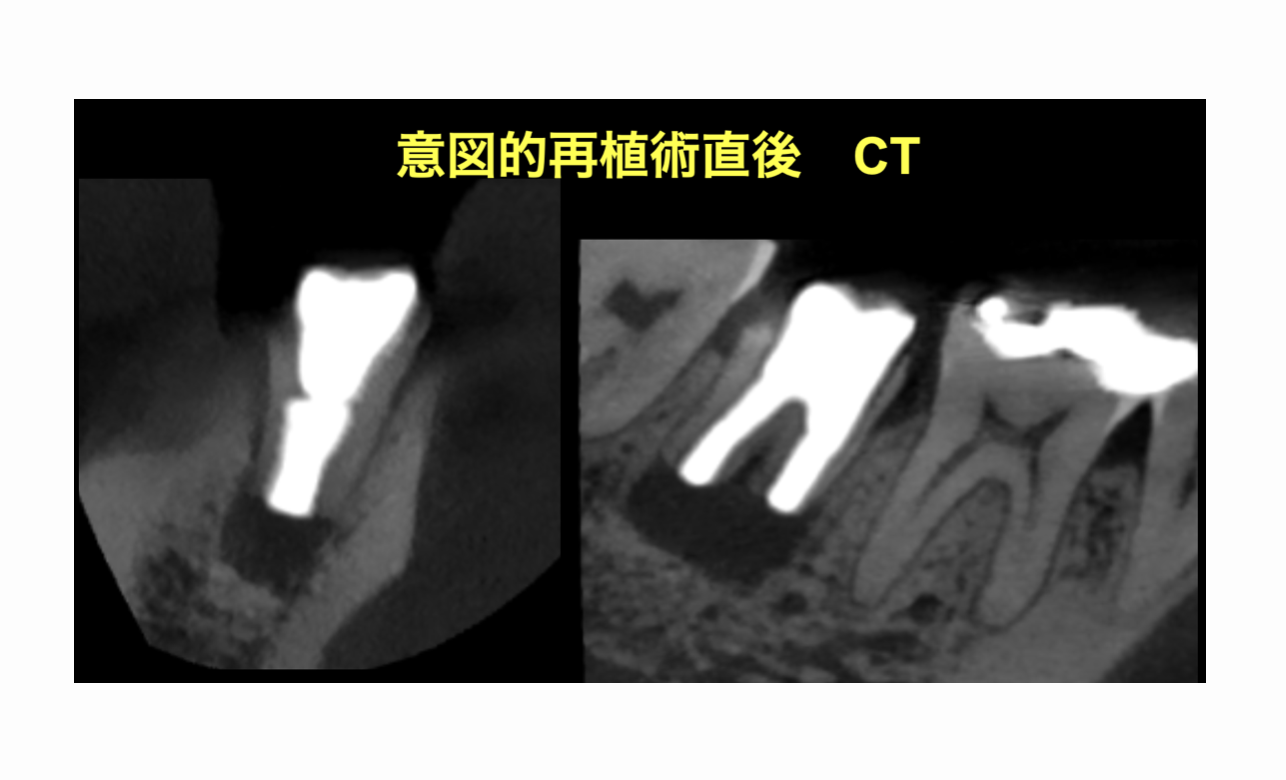

意図的再植術 1年6ヶ月後の経過

| 治療の方法 | 意図的再植術 |

意図的再植術を行うこととなった。